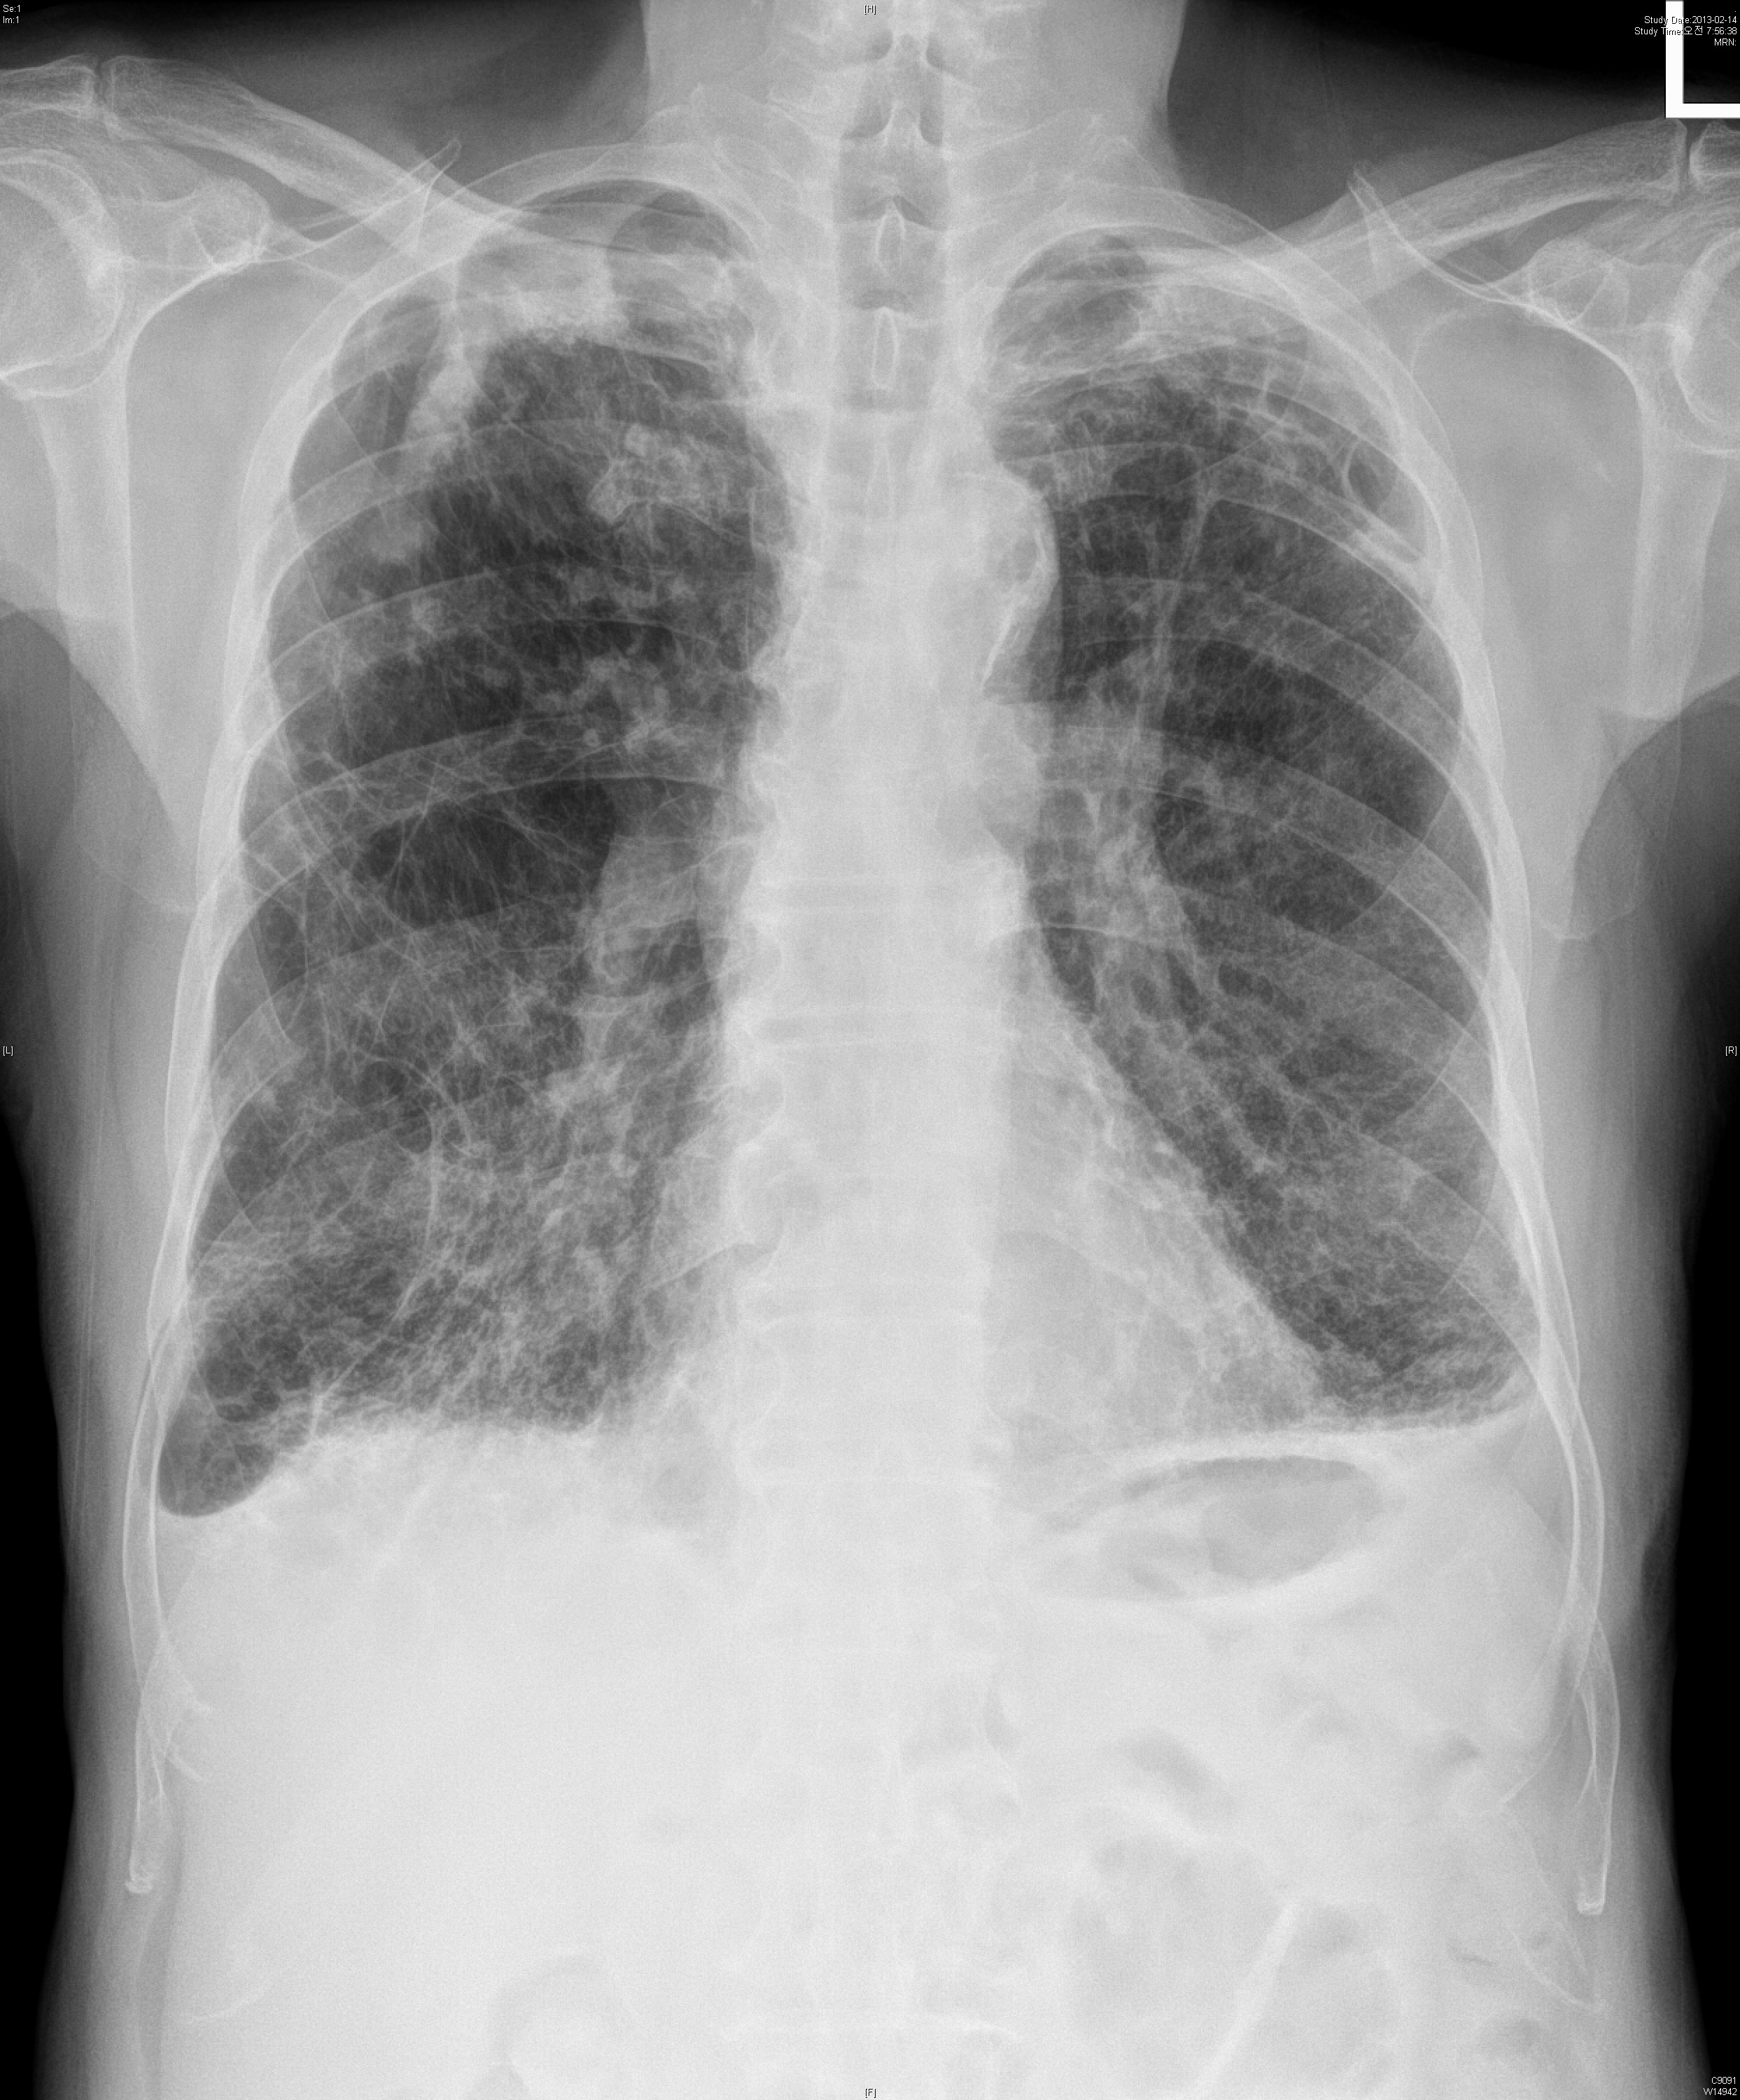

74¼¼ ³²È¯À¸·Î COPD grade A, CAOD, prostate cancer ·Î f/u ÁßÀ̾ú½À´Ï´Ù.

¾à ¿­Èê ÀüºÎÅÍÀÇ °¡½¿ ÅëÁõ ¹× È­³ó¼º °´´ãÀ» ÁÖ¼Ò·Î ³»¿øÇÏ¿´½À´Ï´Ù.

ÁÂÃøÇϺο¡¼­ crackles ûÁøµÇ¾ú½À´Ï´Ù.

6°³¿ù ÀüÈÄÀÇ »çÁøÀÔ´Ï´Ù.